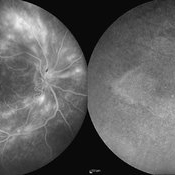

Cystoid Macular Edema (CME)

Cystoid Macular Edema (CME)

Sep 11 2012 by Hamid Ahmadieh, MD

Wide-field FA & ICG angiography imagings of a 17-year-old boy with CME & retinal periphlebitis secondary to chronic intermediate uveitis.

Photographer: Hamid Ahmadieh, MD, Ophthalmic Research Center, Labbafinejad Medical Center, Shahid Beheshti University of Medical Sciences

Imaging device: Heidelberg Spectralis

Condition/keywords: cystoid macular edema (CME), indocyanine green (ICG) angiography, intermediate uveitis